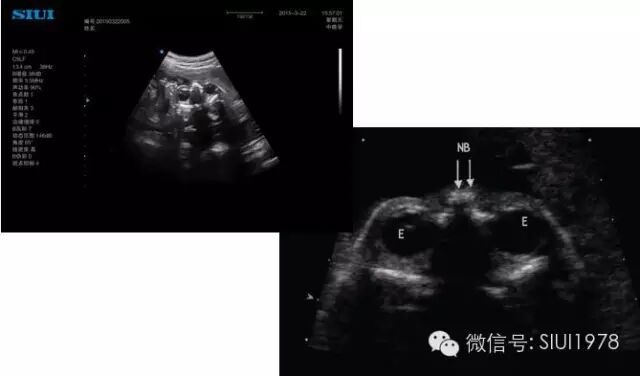

(一)双眼球水平横切面

1.扫查方法:声束平面通过双侧眼球,横切胎儿头部即可获得,声束尽可能从前面进入并与双侧眼球中部边线垂直。这是进行胎儿颜面部横断扫查的基准切面。

2.判断标准:要求在同一平面内显示双侧晶体及眼球图像,且双侧晶体及眼球大小基本相等。此外,该切面还可显示眼眶骨性高回声、鼻根部骨性高回声及颅内结构。

双眼球水平横切面

3.主要观察的解剖结构及内容:

(1)眼球:双侧眼球及眼球内晶体大小基本相等,晶体内部为无回声。

(2)眼眶的大小、 眼内距及眼外距:眼眶的大小又称眼距是指眼眶的左、 右径;眼内距是指双侧眼眶内侧壁的距离;眼外距是指双侧眼眶外侧壁的距离。20周以上胎儿正常时眼内距约等于眼距。

(3)鼻根部骨性结构:呈三角形,前上端窄小,由一对鼻骨板构成,下端宽大,由位于两侧上颌骨额突构成。双侧鼻骨在中线汇合。

4.临床意义:双眼球横切面是颜面部系列横切面的基准切面,尤其在显示上唇及上腭时,双眼球横切面是一个非常重要的参照平面,对准确判断是否存在唇腭裂有非常重要的意义。该切面可明确诊断一侧或两侧小眼畸形、无眼畸形、独眼畸形、先天性白内障、眼距过近、眼距过远。对鼻骨发育不良、缺失、鼻发育不良等有辅助诊断价值。